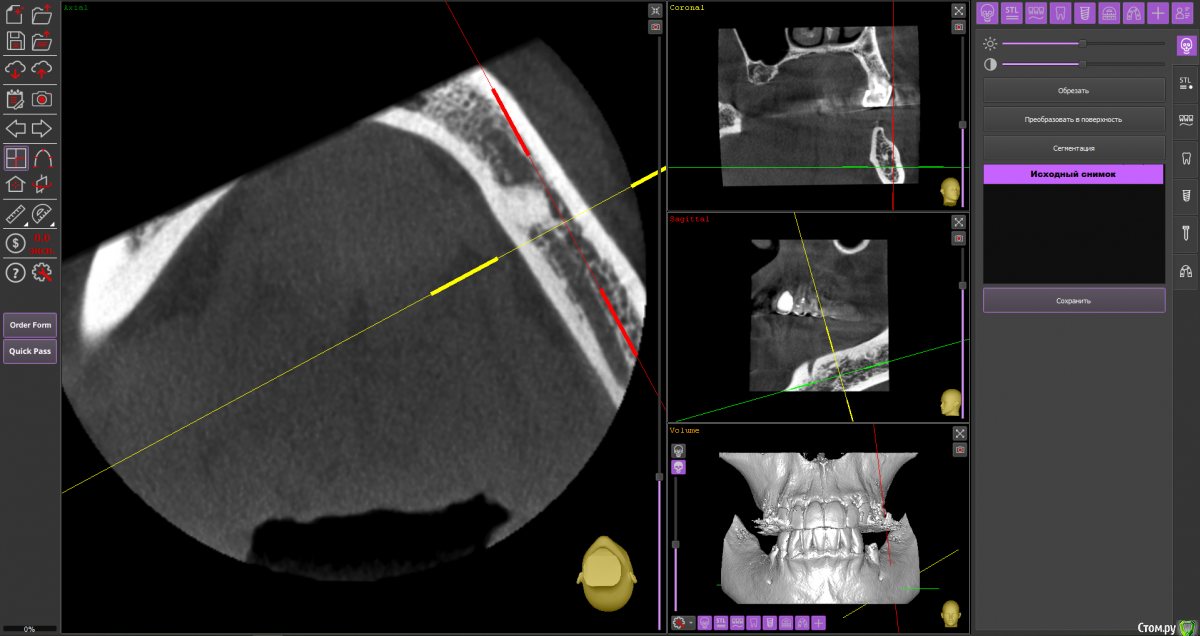

almaz7888 Опубликовано 11 февраля, 2021 Поделиться Опубликовано 11 февраля, 2021 (изменено) Доброе утро коллеги! Подниму тему. Данной пациентке планируется имплантация для замещения концевых дефектов на нижней челюсти. Зуб 3.5 думал удалить во время операции. Образование в области 3.5 это просто склероз кости? В области ментального отверстия справа также имеется какой-то очаг но меньших размеров. Изменено 11 февраля, 2021 пользователем almaz7888 Ссылка на комментарий